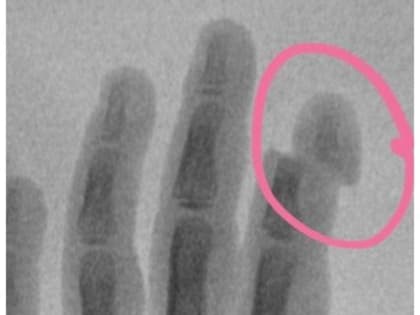

Детская коляска обрубила палец девочке из Подмосковья

5-летняя девочка поступила с травмой указательного пальца в Московскую областную детскую клиническую травматолого-ортопедическую больницу (МОДКТОБ): ногтевая фаланга буквально держалась за счет кожи.